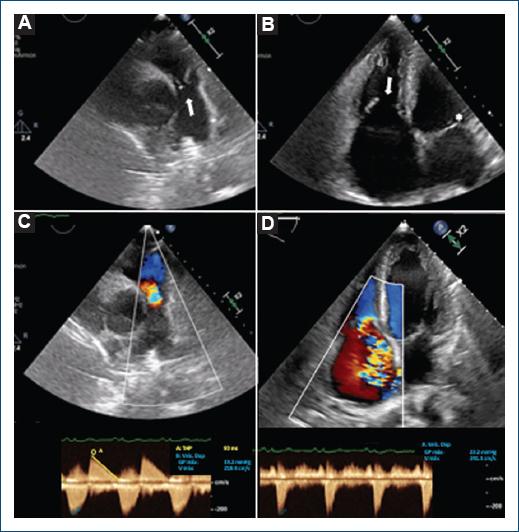

He was admitted with a 4-day history of abdominal pain, jugular plethora, and edema of the lower extremities. The echocardiogram highlighted severe dilation of the right cavities, with thickening, stiffness, and immobility of the pulmonary and tricuspid valves (Figs. 2A and B), with a fixed and semi-open position throughout the heart cycle, conditioning systolic-diastolic free flow between the right cavities and the trunk of the pulmonary artery (Figs. 2C and D). After treatment for right heart failure, the patient was asymptomatic. Due to advanced and treatment-resistant NET-CS, in addition to progressive heart disease, surgical valve replacement was not considered, and he died 6 months later.

Figure 2 Echocardiogram during admission. A: the short parasternal axis shows the pulmonary valve with thickened and semi-open leaflets in the diastolic phase (cusp separation of 9.9 mm) (arrows). B: the tricuspid valve is seen with thickened and semi-open leaflets in the systolic phase, with a separation of its cusps of 16-17 mm (arroz), while the mitral valve is closed (asterisk). C: using color Doppler, free regurgitant diastolic flow is observed between the right ventricle and the trunk of the pulmonary artery, with 70% occupation of the pulmonary annulus and maximum density pan-diastolic Doppler. The continuous Doppler half-pressure time is 90 ms. The opening of the pulmonary valve is not restricted (slight increase in the maximum systolic velocity of 2.2 m/s, due to the hyperflow component of severe insufficiency). D: in the tricuspid valve, systolic free flow between the right atrium and the ventricle is notable, making it impossible to quantify the regurgitant volume using the PISA method. Continuous Doppler is dense, triangular, with a peak velocity of 2.3 m/s, and it is not suitable for estimating pulmonary pressure. The valve opening is not restricted (peak diastolic velocity < 2 m/s).